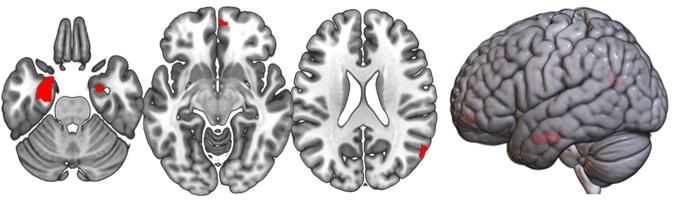

There is a lack of knowledge regarding the relationship between proneness to dimensional psychopathological syndromes and the underlying pathogenesis across major psychiatric disorders, i.e., Major Depressive Disorder (MDD), Bipolar Disorder (BD), Schizoaffective Disorder (SZA), and Schizophrenia (SZ). Lifetime psychopathology was assessed using the OPerational CRITeria (OPCRIT) system in 1,038 patients meeting DSM-IV-TR criteria for MDD, BD, SZ, or SZA. The cohort was split into two samples for exploratory and confirmatory factor analyses. All patients were scanned with 3-T MRI, and data was analyzed with the CAT-12 toolbox in SPM12. Psychopathological factor scores were correlated with gray matter volume (GMV) and cortical thickness (CT). Finally, factor scores were used for exploratory genetic analyses including genome-wide association studies (GWAS) and polygenic risk score (PRS) association analyses. Three factors (paranoid-hallucinatory syndrome, PHS; mania, MA; depression, DEP) were identified and cross-validated. PHS was negatively correlated with four GMV clusters comprising parts of the hippocampus, amygdala, angular, middle occipital, and middle frontal gyri. PHS was also negatively associated with the bilateral superior temporal, left parietal operculum, and right angular gyrus CT. No significant brain correlates were observed for the two other psychopathological factors. We identified genome-wide significant associations for MA and DEP. PRS for MDD and SZ showed a positive effect on PHS, while PRS for BD showed a positive effect on all three factors. This study investigated the relationship of lifetime psychopathological factors and brain morphometric and genetic markers. Results highlight the need for dimensional approaches, overcoming the limitations of the current psychiatric nosology.

目前,人们对于精神障碍的发病机制和潜在病理生理学之间的关系知之甚少,而这种关系在多种主要精神障碍中都存在,如重性抑郁障碍(MDD)、双相障碍(BD)、分裂情感性障碍(SZA)和精神分裂症(SZ)等。使用 OPerational CRITeria(OPCRIT)系统对符合 DSM-IV-TR 标准的 1038 名 MDD、BD、SZ 或 SZA 患者的终生精神病理学进行了评估。将队列分为两个样本进行探索性和验证性因素分析。所有患者均采用 3-T MRI 扫描,使用 SPM12 中的 CAT-12 工具箱进行数据分析。精神病理因子评分与灰质体积(GMV)和皮质厚度(CT)相关。最后,使用因子评分进行探索性遗传分析,包括全基因组关联研究(GWAS)和多基因风险评分(PRS)关联分析。确定并交叉验证了三个因子(妄想幻觉综合征、PHS;躁狂、MA;抑郁、DEP)。PHS 与包括海马体、杏仁核、角回、中顶叶和中额叶回在内的四个 GMV 簇呈负相关。PHS 还与双侧颞上回、左顶下叶和右角回的 CT 呈负相关。其他两个精神病理因子没有发现显著的脑相关。发现 MA 和 DEP 与全基因组显著相关。MDD 和 SZ 的 PRS 对 PHS 有正向影响,而 BD 的 PRS 对所有三个因子都有正向影响。本研究调查了一生中精神病理因子与脑形态计量和遗传标记的关系。研究结果强调了需要采用多维方法,克服当前精神病学分类法的局限性。